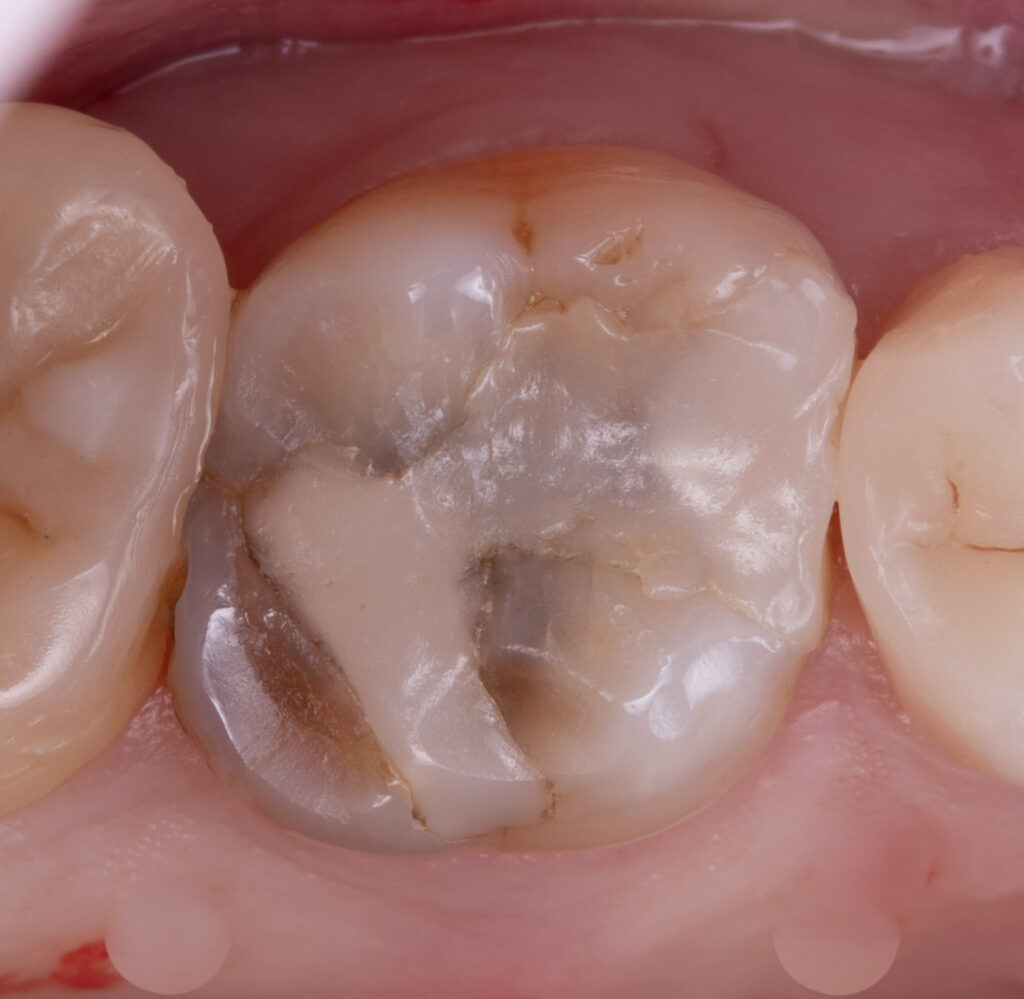

Wooden wedges and a Palodent matrix system were applied to ensure proper embrasure and facilitate proximal wall restoration. The proximal walls were rebuilt using Asteria A2B composite, and EverX Bulk Fill was placed inside the tooth to reduce stress, minimizing the C-factor and polymerization stress. The tooth anatomy was subsequently restored with NeoSpectra in shades A2 and D1, and the fissures were stained with Mecherium Color Brown.